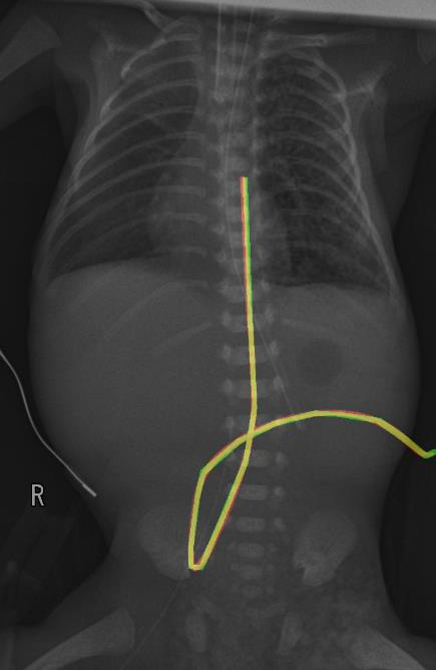

- 모델 출력: 영상과 동일한 크기의 카테터 영역이 표시된 이진 마스크 이미지로, 그 예시는 아래와 같음 (빨간색: 모델 예측 영역, 초록색: 정답 영역, 노란색: 모델이 정답을 맞춘 영역)

UVC 분할 결과